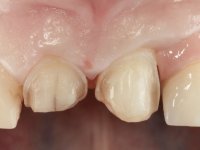

Female patient, 47 years old non-smoker. Tooth 1.3 with endodontic treatment and a cast post and core, rehabilitated with a provisional crown. The two upper lateral incisors are conoid and of small dimension. Tooth 2.2 presents mobility, in agreement with a significant bone reabsorption between teeth 2.1 and 2.3. The two central incisors are separated by a 3 mm diastema and tooth 2.3 presents a crossed occlusion with the opposing tooth. There is also an absence of some posterior teeth and reasonable oral hygiene. In the second intervention performed 8 years later, it was verified that the upper central incisors were chromatically darker and had a longitudinal groove in the enamel which, being pigmented, aesthetically compromised the smile. The work performed in the first phase of the treatment was competent, aesthetically and functionally. Finally, one year after the last intervention, the patient complained of a fracture on the veneer placed on tooth 2.1, probably as a result of being in contact with the abutment of the implant. The rigidity of implant ankylosis may have been the cause of this fracture. I have observed other instances of this type of fracture in identical clinical situations. The veneer of tooth 1.2 was aesthetically compromised and the dental structure itself had small caries and, therefore, its replacement would be recommended.

• Confection and bonding of a new feldspathic veneer to replace the fractured one. The new veneer should include a greater distal inter-proximal dental area from tooth 2.1.

• Replace tooth 1.2 veneer with a total crown in feldspathic ceramics, or by a now called 360 veneer.

The axis of insertion of the veneer in relation to the abutment was very carefully evaluated. The feldspathic veneers were prepared in the laboratory and then bonded to the mouth after placing absolute insulation. One year later, we began our third phase of treatment, after the veneer in tooth 2.1 fractured. A dental preparation was done on the bonded veneer, seeking to extend the distal inter-proximal interface more to the palate. The objective would be to move the veneer to a more palatine contact point. Preparation of tooth 1.2 was limited to creating an insertion axis. After preparation, the total crown and laboratory veneer were bonded to the mouth. First, the crown was bonded using a relative insulation with Teflon, later the veneer was bonded after the absolute insulation placement. In the crown, I used this type of insulation to avoid the use of staples. It would be difficult to apply due to the shape and size of the tooth, and would also be aggressive to the soft tissues. After bonding procedures, the occlusal integration of the work was evaluated.